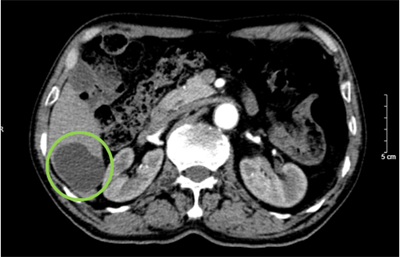

Điều trị Ung thư biểu mô tế bào gan giai đoạn tiến xa tại Trung tâm Y học hạt nhân và Ung bướu - Bệnh viện Bạch Mai Ngày đăng: 30/01/2026 Ung thư biểu mô tế bào gan (Hepatocellular carcinoma –HCC) là loại ung thư gan nguyên phát thường gặp nhất, chiếm khoảng 75–85% tổng số các trường hợp ung thư gan. Theo số liệu GLOBOCAN 2022, ung thư...

Ca lâm sàng: Điều trị ung thư biểu mô tế bào gan bằng thuốc điều trị đích Sorafenib tại Trung tâm Y học hạt nhân và Ung bướu, Bệnh viện Bạch Mai. Ngày đăng: 29/01/2026 Ung thư biểu mô tế bào gan (hepatocellular carcinoma –HCC) là loại ung thư thường gặp đứng thứ hai theo ghi nhận của Tổ chức Globocan Việt Nam năm 2022, ước tính mỗi năm có 24,502 trường hợp bệnh...